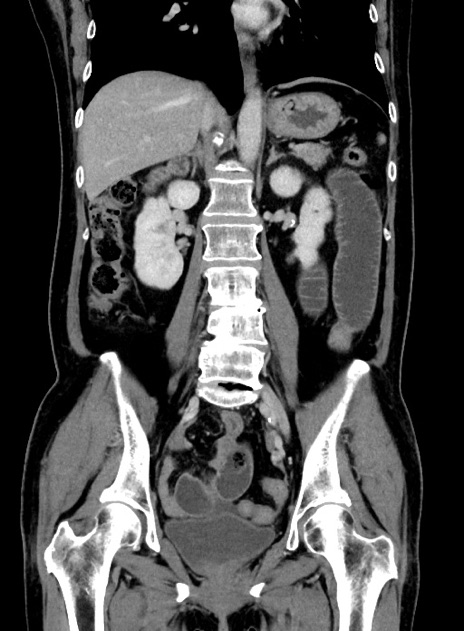

症例9(冠状断像)

【症例】 60歳代女性

【主訴】むかつき、みぞおちの痛み

【現病歴】3日前よりむかつきがあり、食事がとれない。

【既往歴】糖尿病

【身体所見】発熱なし、心窩部圧痛軽度あるも、腹膜刺激症状なし。

【データ】WBC 7400、CRP 1.92